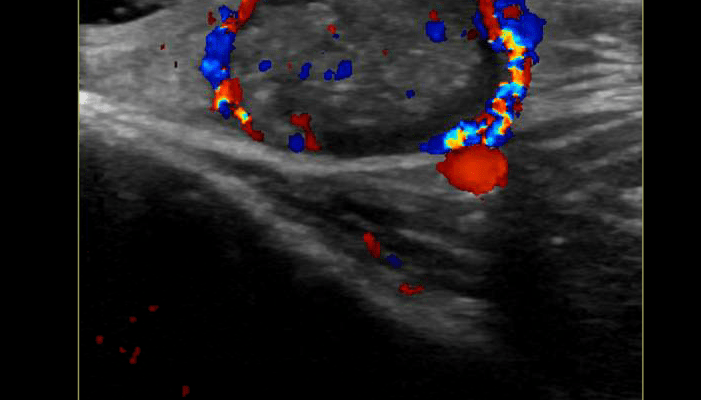

Sonographically you’ll typically see a hypoechoic to mixed echogenicity ovoid structure within the subcutaneous layer. It does not extend deep to the fascia. It can have echogenic calcifications within

the lesion, there is also usually good posterior acoustic enhancement.

Color doppler usually shows intralesional flow, whereas a dermoid cyst or other

similar lesion will not have internal flow.